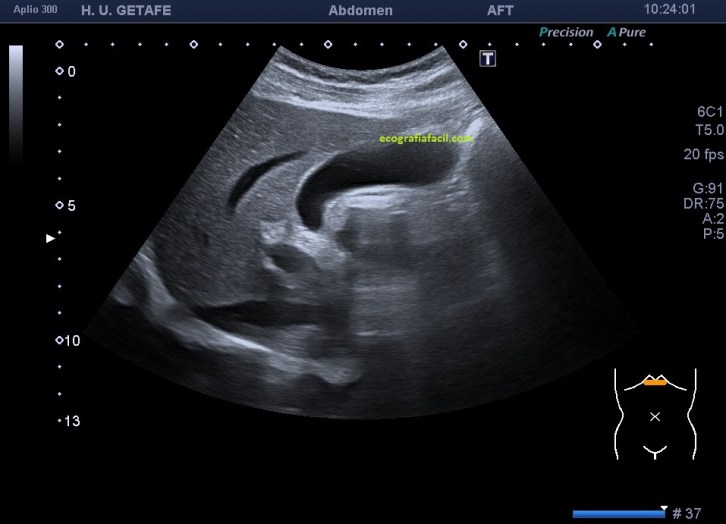

En este imagen ves una vesícula estudiada en longitudinal, con abordaje transcostal, muy similar a la imagen número 1, pero completamente distinta. En esta ocasión ves una vesícula heterogénea y ecogénica con diferentes ecogenicidades internas que corresponden a las diferentes densidades que presenta el líquido dentro de la ecoestructura. Es la típica manera en la que encontramos las vesículas con barro y sin litiasis.

Podemos encontrarnos niveles hidro-hidro, donde podemos ver, el contenido biliar normal, anecoico como en la imagen 1, con barro, cuya ecogenicidad correspondería con la imagen 2 y tendrías la imagen 3.